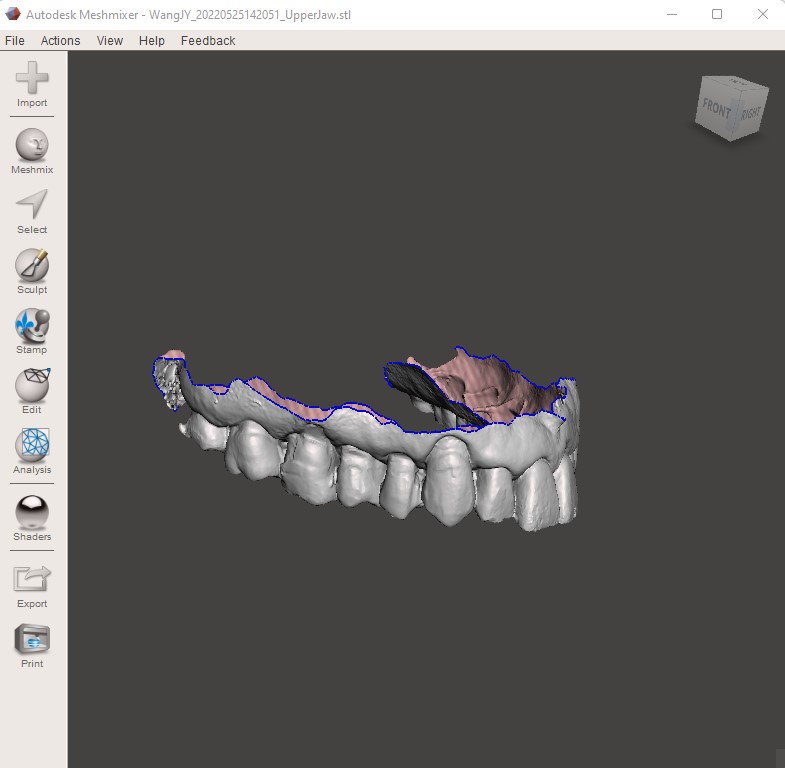

To be able to deliver in house aligners a clinician should have

- digital scanner

- orthodontic software to plan movement

- 3D printer

- POSITIVE Pressure THERMOform machine

With experience and careful planning the clinician becomes more confident of delivering great clinical outcomes consistently. Having just the first two components, the digital scanner and the software, would already give the clinician the advantage of control over the case compared to using a third party provider.